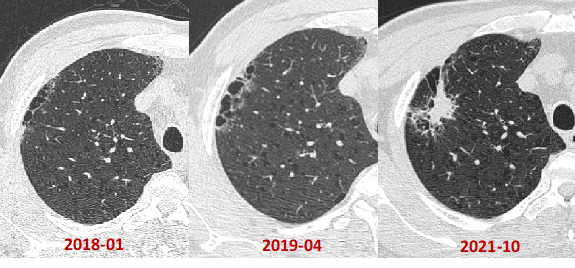

·      男性,80岁,右下肺疤痕癌,病灶内部可见不规则钙化灶,未见肿大淋巴结。

·      病理:右下肺浸润性腺癌(pT2aN0M0,IB期)

·      这是一个缓慢进展型的肺癌,随访3.5年结节无明显变化。